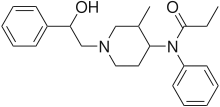

Anilidopiperidines

- 3-Allylfentanyl

- 3-Methylfentanyl

- 3-Methylthiofentanyl

- 4-Phenylfentanyl

- Alfentanil

- α-Methylacetylfentanyl

- α-Methylfentanyl

- α-Methylthiofentanyl

- Benzylfentanyl

- β-hydroxyfentanyl

- β-hydroxythiofentanyl

- β-Methylfentanyl

- Brifentanil

- Butyrfentanyl

- Carfentanil

- Fentanyl

- Lofentanil

- N-Methylcarfentanil

- Mirfentanil

- Ocfentanil

- Ohmefentanyl

- Parafluorofentanyl

- Phenaridine

- R-30490

- Remifentanil

- Sufentanil

- Thenylfentanyl

- Thiofentanyl

- Trefentanil

Structures